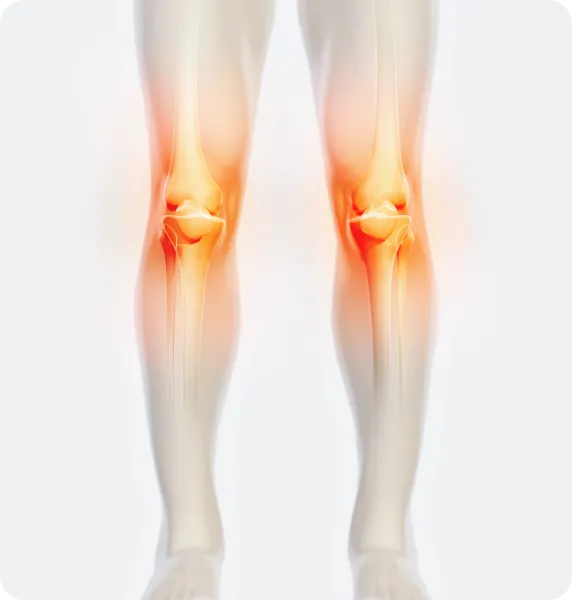

O다리

• 무릎이 외측으로 벌어지면서 다리 축이 변형됨

• 체중부하가 다리 안쪽(내측)에 집중되어 내측 관절의 압력증가로

무릎관절의 퇴행성 변화와 통증을 초래

• 허벅지 안쪽 근육이나 엉덩이 근육이 약화되면 무릎 안정성이 떨어져 내반슬이 악화

X다리

• 무릎이 안쪽으로 모이면서 다리 축이 변형됨

• 체중 부하가 다리 바깥쪽에 집중되어 외측 관절의 압력증가로

무릎 통증, 불안정성, 관절 손상을 유발할 수 있음

• 허벅지 바깥쪽 근육이 과도하게 발달하고 안쪽 근육이 약화되면 외반슬이 진행

무릎

무릎 관절 안팎으로

휘거나 틀어짐